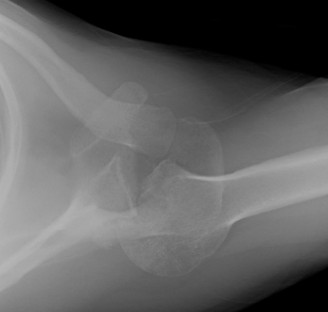

A 45-year-old carpenter presents with shoulder pain that has been ongoing for the last 3 months. He denies any significant injury. He describes night pain and significant discomfort at work. His imaging is shown in Figure 2–9. What is the most likely diagnosis?

🔍 Click to enlargeClinical Radiograph / Orthopedic Image

Figure 2–9_From Shi LL, Mullen MG, Freehill MT, et al. Accuracy of Long Head of the Biceps Subluxation as a Predictor for Subscapularis Tears. _Arthroscopy 2015;32(4):615–619.

Discussion

The correct answer is (A). Medial subluxation of the biceps tendon as seen in this MRI is commonly associated with a tear of the subscapularis tendon which attaches to the lesser tuberosity. This patient’s pain may in part be attributable to the subscapular tear and this should be evaluated for during physical examination. Supraspinatus tears (Answer B) cannot be easily visualized on axial views and are not associated with medial biceps subluxations. A labral tear and ALPSA lesion (Answers C and D) are not seen on the images provided. The question stem and MRI are not suggestive of shoulder instability (Answer E). Objectives: Did you learn...? Diagnose and treat acute rotator cuff tears?